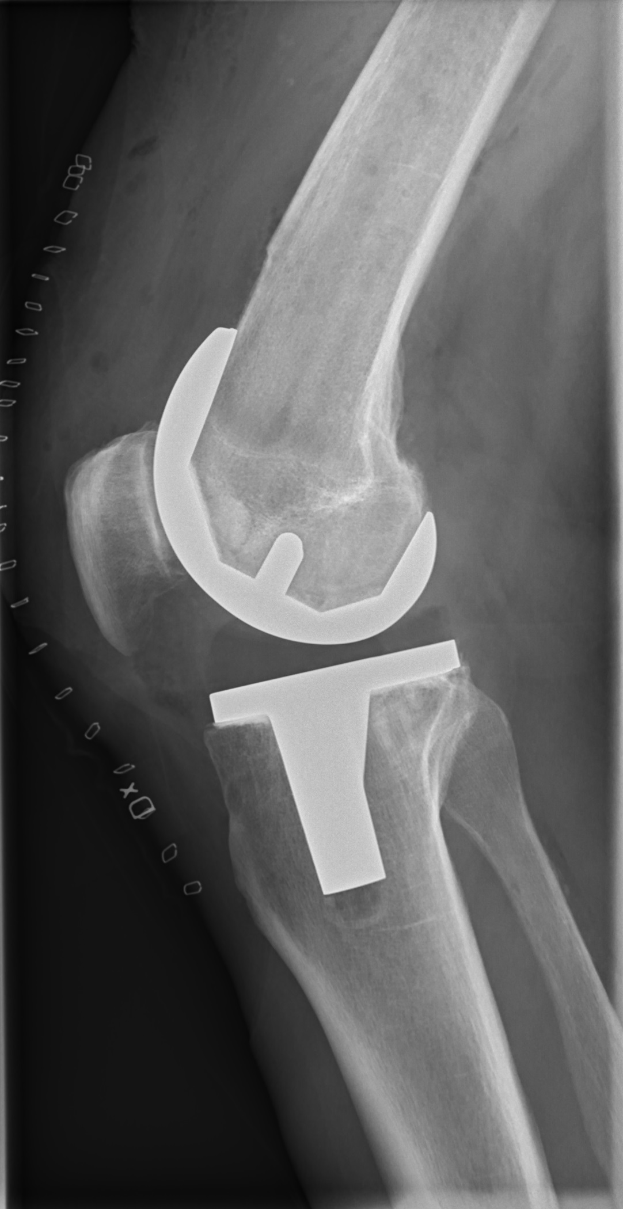

Ein Röntgenbild eines menschlichen Beins, das einen Bruch im Kniebereich zeigt, mit einem sichtbaren Band.Sylvio Thies